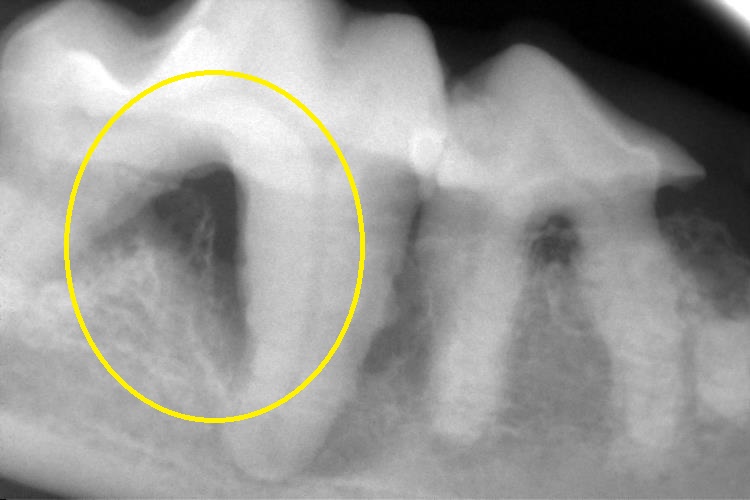

レントゲン検査

下顎左右第1後臼歯です。

歯根部に吸収病巣が認められました。